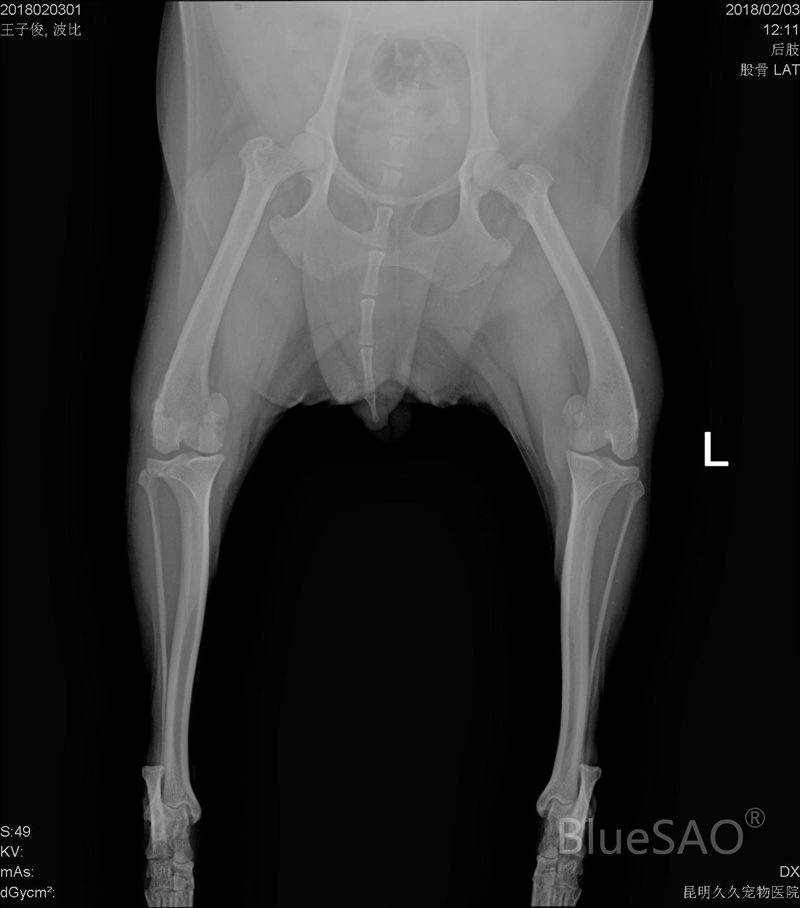

Preoperative DR image(2018):

Poodle, named Bobby, 7 years old, female, neutered. In July 2018, she was diagnosed with a grade Ⅲ medial luxation of the patella. Patellar groove replacement (PGR) and TTTT were used in the surgery. During the surgery, theBlueSAO PGR-2# prosthesis was used for PGR. In 2020, the Kirschner wires of TTTT were loosened, so the Kirschner wires were removed. The re-examination in July 2021 showed that she recovered well. The implantation time of the PGR prosthesis is 3 years, and the current state is stable.